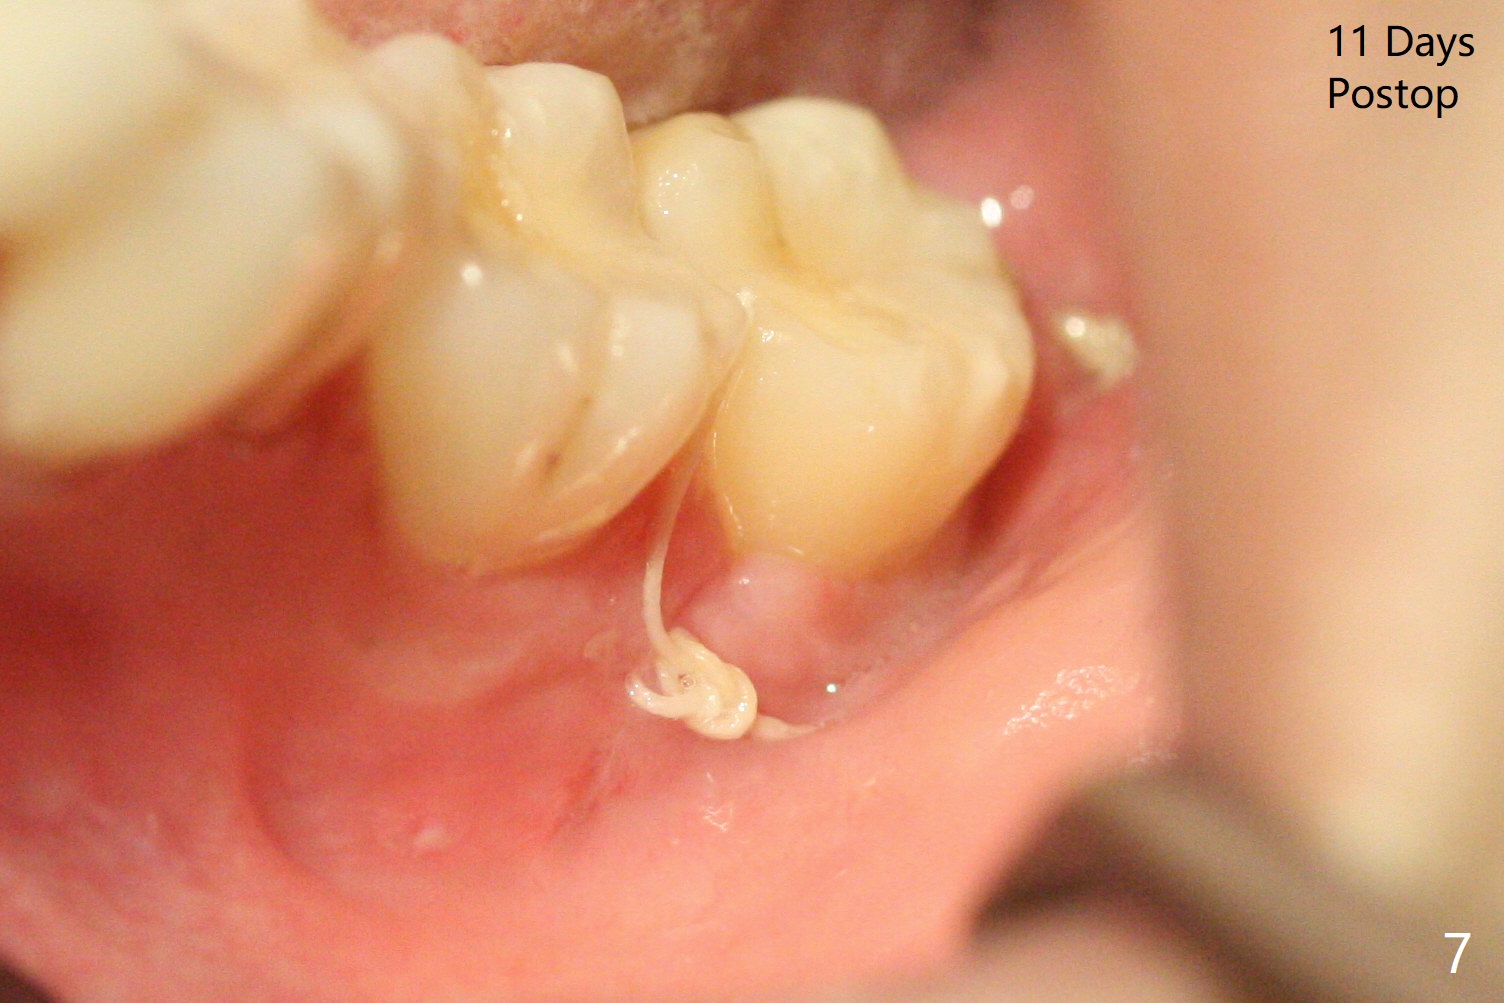

A 27-year-old woman (nervous) is going to return for #16 and 17 extraction (Fig.1). Offer sedative (Valium) if she cannot overcome fear. Take PAs for #17 and 32 to confirm Buccal Impaction, which dictates position of the accessory incision to reduce loss of bone graft in case of wound dehiscence. Place Collagen Plug (1/2 piece) in the apical portion of the sockets of the lower 3rd molars, while Augma and Osteogen Plug (1 piece) in the coronal half of #17 and 32, respectively. Place additional Collagen Plug for the remaining socket if needed before 4-0 PGA suturing as the 2nd step to decrease the chance of losing bone cement. Preop PA shows that the tooth #17 seems to be mesial (Fig.2 arrow). The accessory incision is placed mesiobuccal of the tooth #18 (Fig.4 red oblique line, Fig.6) so that it is not overlying the bony defect (Fig.4 arrowheads). Since the access to the impacted tooth is limited, small field of CT is taken (Fig.3,4), which shows the root is yet to be exposed (Fig.3 R). After tooth removal, Collagen plug is placed in the apex of the socket for hemostasis (Fig.5 C), while Bond Apatite coronal for bone regrowth (A). There is no dehiscence 11 days postop (Fig.7), although the patient complains of pain in the jaw and the temporomandibular region. The anterior portion of the external oblique ridge forms 1 year 7 months postop (Fig.8).